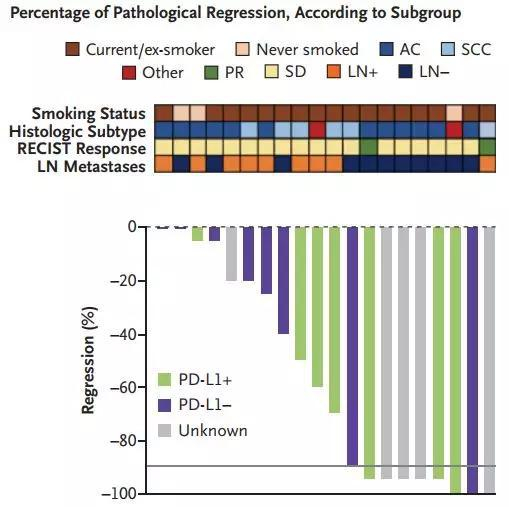

以当今医学和生命科学发展的步伐,12年都沧海桑田了,所以业内专家普遍呼吁,把病理学显著缓解作为评价新辅助化疗效果的指标。而这个显著缓解,指的是切除的肿瘤和淋巴结中,癌细胞的占比低于10%[7]。

当然,肺腺癌和肺鳞癌的显著缓解效果也有区别,鳞癌需要相对较高的缓解程度才能实现获益,但腺癌的癌细胞比例只需要降到60%左右

如果达到了这个数字,就意味着新辅助治疗已经充分实现了术前杀灭癌细胞的目的。从过往研究来看,病理学显著缓解比客观缓解率(ORR)更能反映患者预后[8],预测DFS和OS时间,也已经有FDA认可的先例。

当然,机遇和挑战同在。拿生物标记物来说,肿瘤突变负荷(TMB),在CheckMate-159试验中就与患者的新辅助疗效有关,突变数量越多,疗效就相对越好,这也符合了免疫新辅助治疗利用大量新抗原的道理。

但是治疗晚期患者时有指导意义的PD-L1表达情况,在CheckMate-159试验和Tecentriq+化疗的试验中都没体现价值[13]。会不会还有其他的生化标记物,比如T细胞亚群,等待着后续试验的挖掘呢?

PD-L1阳性效果好,但是阴性也不差呢……